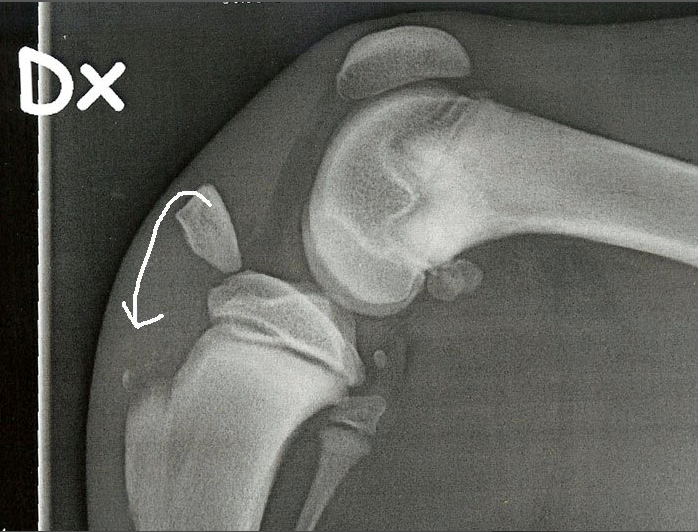

Please look below at all these x-rays from last years random friend’s injuries ( and these are without even searching as these happen all the time). If it is not a growth plate , it is a neck, back, wrist, hock, ribs or any large bones for that matter. One of the most common example is when a small piece of the knee joint splits, which end up in a 2-3000€ surgery. I do not see much point in taking such a huge risk, so don’t run adults and pups! Period!

Here is the proof! More info after the pictures!

• The diagrams below show the different type of fractures (the blue line represents the soft growth plate tissue, the red line represents the fracture line, and the speckled red line is a crushed growth plate).

Common locations of the various Salter-Harris growth plate fractures in dogs and cats • Type1 – hip joint (slipped femoral capitis), knee (distal femur)

• Type 2 – knee (distal femur)

• Type 3 – elbow (distal humerus)

• Type 4 – elbow (distal humerus)

• Type 5 – 1. wrist or carpus (distal ulna or the distal radius less commonly), this results in an angular limb deformity); 2. ankle or hock (distal tibia)